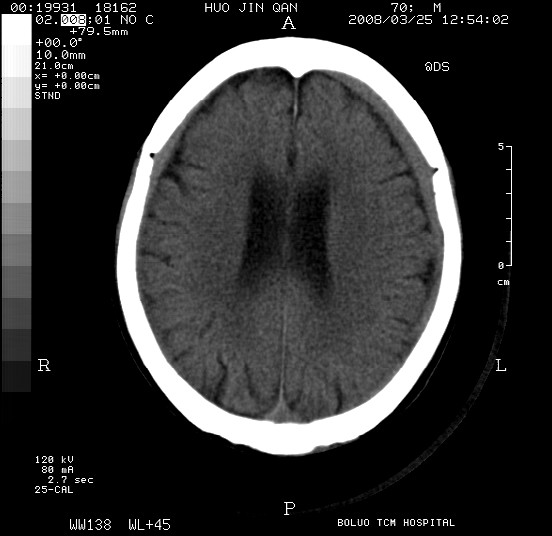

以下是引用随光逐影在2008-3-25 20:15:00的发言:[br]双侧额颞顶部亚急性(或慢性)硬膜下血肿。

以下是引用liuyue在2008-3-26 18:57:00的发言:[br]以下是引用随光逐影在2008-3-25 20:15:00的发言:[br]双侧额颞顶部亚急性(或慢性)硬膜下血肿。 [br]支持![br]可以无明显外伤病史,老年人可以在激烈摇晃或轻微头部碰创头部时,发生硬膜下出血.